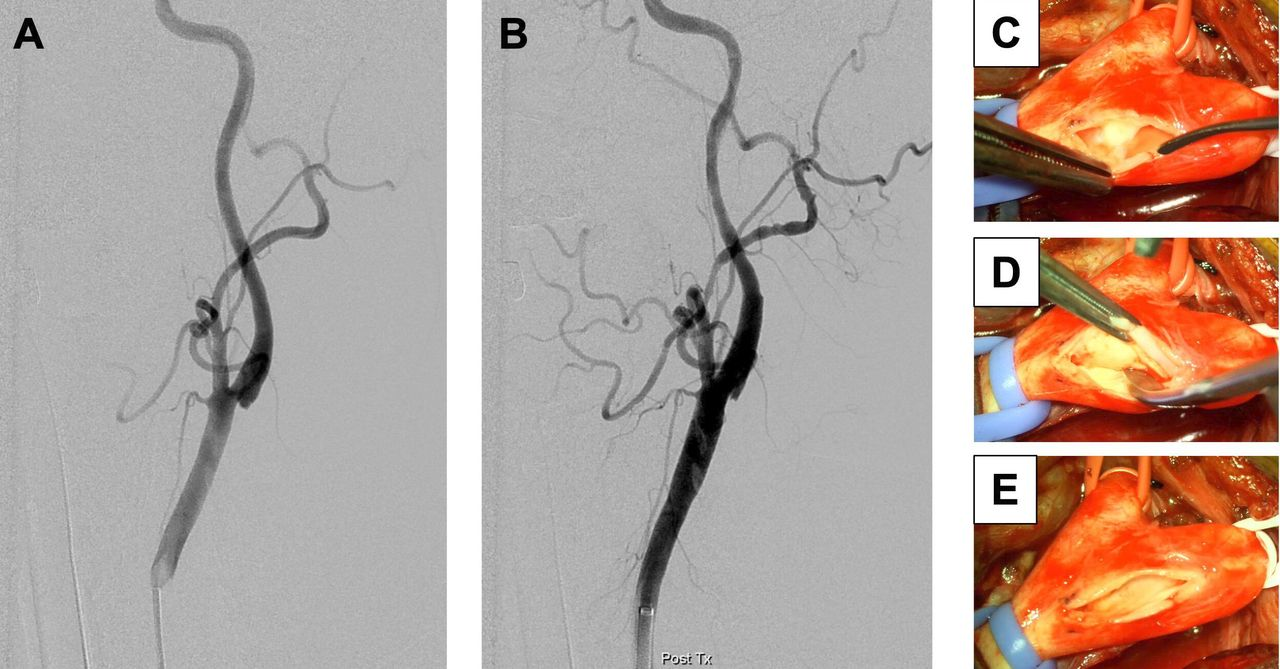

How does it appear in carotid angiogram and in real time per-operative ?

Images : Chen H, Colasurdo M, Costa M, Nossek E, Kan P. Carotid webs: a review of pathophysiology, diagnostic findings, and treatment options. J Neurointerv Surg. 2024 Nov 22;16(12):1294-1298. doi: 10.1136/jnis-2023-021243. PMID: 38290814.